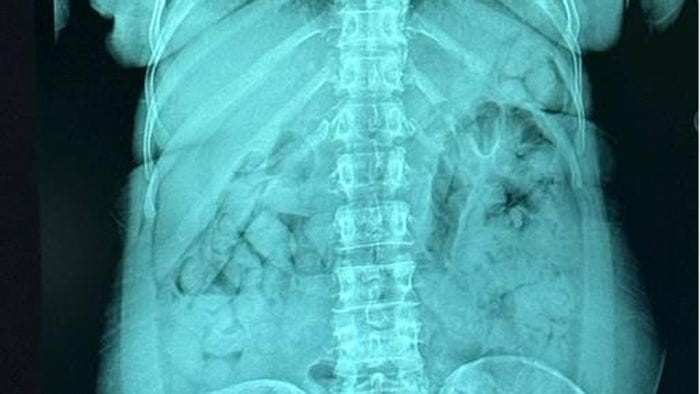

Ingerisce 120 ovuli, oltre un chilo di eroina nello stomaco: donna arrestata in aeroporto - Una donna di 46 anni, di origine nigeriana e residente in Italia dal 2013, è stata arrestata dopo essere stata sorpresa con 120 ovuli di eroina ... Da ecodibergamo.it

Nello stomaco 120 ovuli con oltre un chilo di eroina, donna arrestata all’aeroporto di Orio - La sostanza stupefacente trasportata con la tecnica dei body packer ... Da bergamonews.it